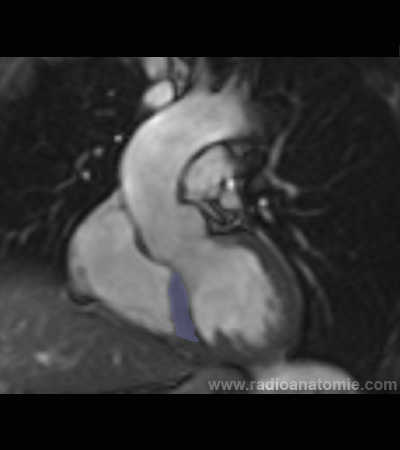

Chambre de chasse du ventricule gauche LVOT2

Plan valve aortique

Plan chambre de chasse du ventricule gauche (LVOT)

Valve aortique

Muscles papillaires

Ventricule gauche

Ventricule droit

Oreillette droite

Aorte ascendante

Artère pulmonaire

Septum interventriculaire